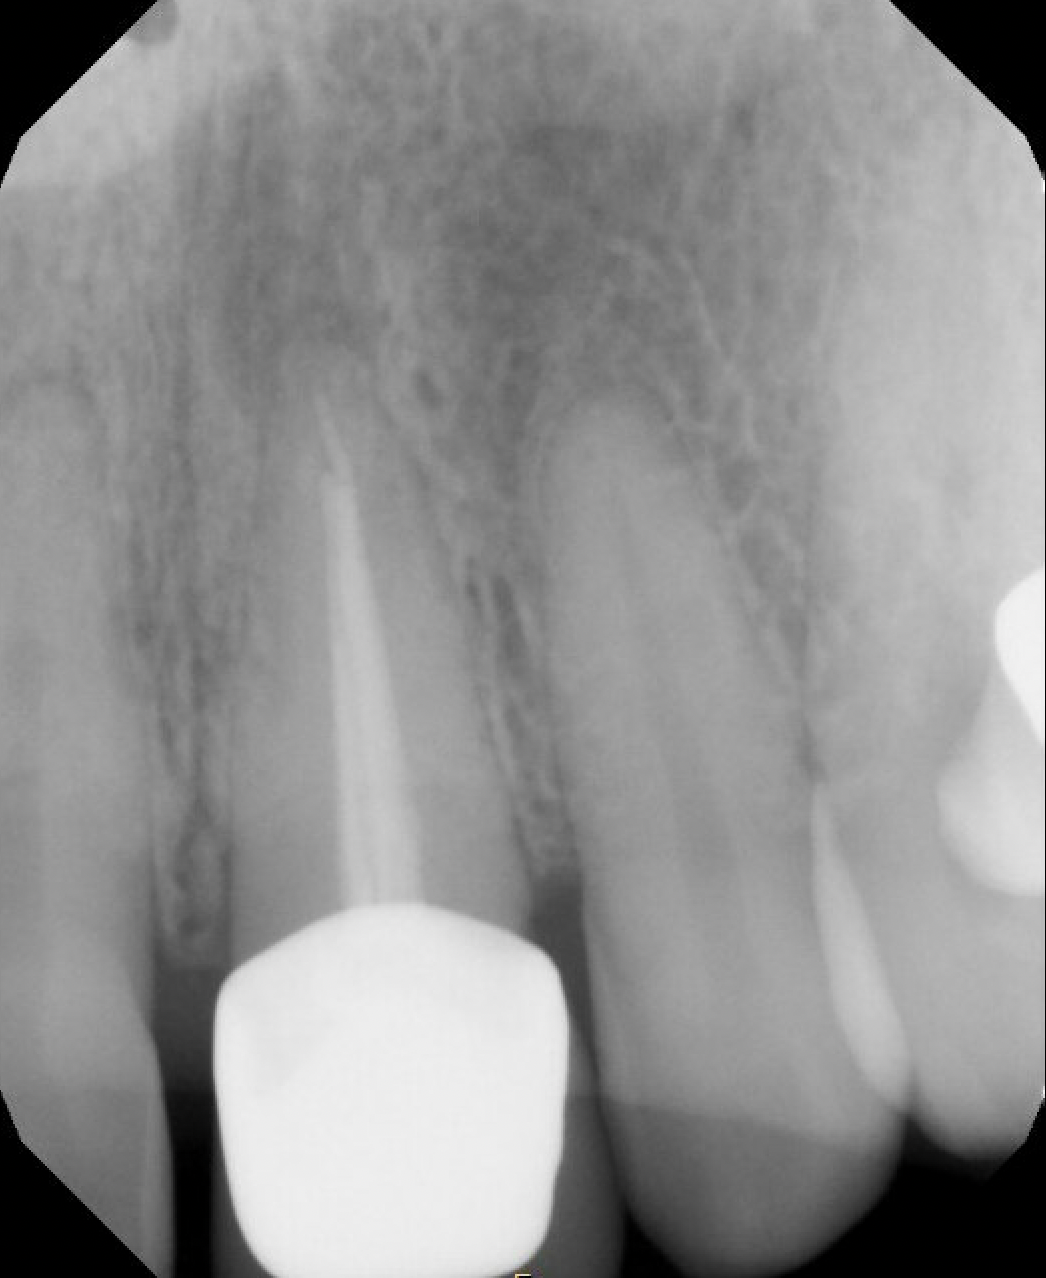

#9 S-RCT